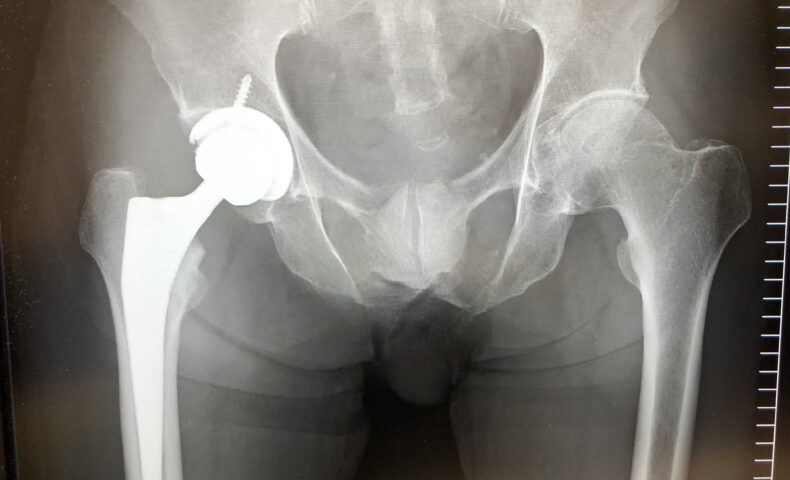

検診の前にX線を撮りに行きました。

・Dr. :あまり無理しないように。X線では問題ないようです。(アイキャッチ画像参照願います。)それではtaoさん、傷口を見たいので横になってください。(診察台に寝て傷口を見せる。防水テープっやネット包帯をはがす。)ネット包帯が2箇所ある。